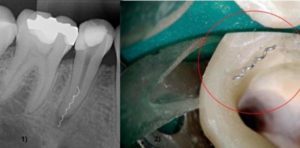

- Даже настоящий профессионал в своем деле не застрахован он случайностей. Например, при обработке зубной полости тончайшими стоматологическими инструментами, всегда существует риск того, что небольшой кусочек отломится и застрянет в канале. Однако хороший специалист всегда проверяет результат своей работы на рентгене. Если этого не произошло и вас сильно беспокоит зубная боль после пломбирования каналов, обязательно проведите рентгеновское обследование с целью выявления присутствия в полости зуба посторонних предметов.

Если пломбу поставили качественно, но человеку все равно больно нажимать на зуб и жевать пищу, можно заподозрить наличие постороннего предмета в зубе. При обработке каналов и зубной полости часть тонкого стоматологического инструмента могла отломиться и остаться внутри, поэтому зуб и заболел. Увидеть посторонний предмет можно с помощью рентгена.

5. Инородное тело

У каждого человека индивидуальный рисунок и толщина нервных каналов, поэтому редко, но при чистке особо сложных участков может отломиться кончик инструмента, потому что сам инструмент довольно хрупкий.

Если врач вовремя заметит это, то может извлечь обломок или же провести депофорез, обеззаразив и герметично закрыв участок с инородным телом.

Но если стоматолог не заметит поломку инструмента, то обломок может вызвать воспаление зубной ткани – и тем самым дискомфорт после лечения.

- Отлом инструмента. Кусочек может оказаться слишком небольшим, чтобы заметить подобное визуально, но в дальнейшем он обязательно даст о себе знать. При подозрении на инородное тело в канале зуба делается рентгеновский снимок.